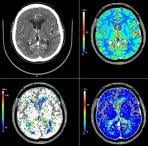

January 6, 2009 - Ziosoft Inc., an advanced visualization and analysis software for medical imaging, today received 510(k) clearance from the FDA for its CT brain perfusion application, which is accessible to clinicians throughout the enterprise using the Ziostation thin-client system.

The brain perfusion application is a powerful analysis tool used with the Ziostation thin-client system. The software is unique in its ability to provide brain perfusion functionality to clinicians as a thin-client application using standard commercial hardware. This software option is designed to aid radiologists in stroke assessment by providing a color map of cerebral blood flow and other perfusion-related parameters from CT images of the brain.

The brain perfusion application includes image manipulation tools as well as measurement tools such as cerebral blood volume, blood flow and mean transit time. Ziosoft’s brain perfusion application provides radiologists with decision support tools to help them assess the type and extent of cerebral perfusion disturbance whether viewed in a hospital or at a remote location offering physicians flexibility and efficiency in viewing solutions.